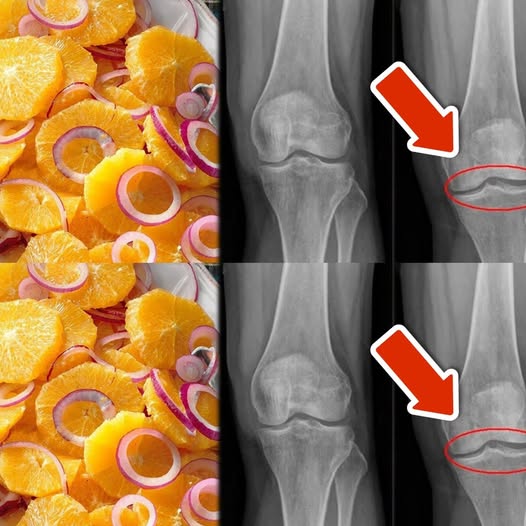

8 Super Easy Ways to Strengthen Your Knees, Cartilage, and Ligaments Using an Orange and Red Onion Mix

Wprowadzenie: Zdrowe kolana, chrząstki i więzadła to podstawa codziennej mobilności i komfortu. Wiele osób szuka naturalnych sposobów na wzmocnienie stawów i redukcję bólu, a…